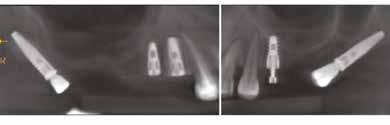

B&B DENTAL PTERYGO IMPLANTS IN ATROPHIC MAXILLAE

The placement of implants in the pterygoid region is a good solution in rehabilitating the posterior atrophic maxillae providing a distal anchorage to improve significantly the support for a fixed restoration avoiding cantelevers or the need to perform additional regenerative surgical procedures. This approach can be referred to as minimally invasive, reducing the complications associated with sinus lift augmentation.

Moreover, the bone that is exploited is native bone instead of being a graft and provides strong cortical anchorage. However, from a surgical-clinical stand point it is more demanding because of the poor visualization of the surgical site, poor access and the presence of vital structures. The exact position of these implants is dictated by the dimension and quality of tuber as well as the anatomy of the maxillary sinus.

The high success rate of the pterygoid implants makes them a good alternative to the standard grafting procedures used in the maxilla.

The protocol for the insertion as well as the topography of pterygoid implants differs from the one of the standard implants due to the different anatomy present in this area. Firstly the clinician must keep in mind that this type of fixture needs to go through different bones namely, initially the maxillary tuberosity into the pyramidal process of the palatine bone to then engage the pterygoid process of the sphenoid bone. The apical threads are designed to condense the soft bone present in the tuber maxillae and to achieve primary stability in the cortical bone of the pterygoid process with a round tip. The mid-coronal portion instead has wider threads for permitting a better anchorage in the spongious bone of the tuber maxillae. Instead the head of the implant is a machined surface for better integration with the soft tissues of the crest.

Studies report success rates around 96.1% with no remarkable clinical complications being reported when compared with conventional implants.

Before the surgical procedure a thorough radiological examination is necessary, with a panoramic x-ray to evaluate the dimension of the tuber maxillae to determine the entry point for the osteotomy and angulation of the implant. The placement of pterygoid implants begins with a crestal incision on the edentulous crest along with a releasing incision, during the elevation of the flap all the maxillary tuberosity needs to be exposed including its posterior aspect for better visualization of the surgical area and to find the surgical landmarks. For the displayed case the preparation of the osteotomy in area 28 began with a pilot drill and was followed by drills with increasing diameter as per protocol to 4,7mm. Both the length of the drill and the location of the osteotomy do not allow for drill irrigation, therefore the osteotomy is performed at low speed rpm.

Thanks to the dense cortical bone surrounding the implant it reached a very high primary stability. Then a B&B Dental EV implant was placed in area 25, before suturing with a polyester 4.0 suture. The extraction socket of the tooth.28 was grafted with B&B Dental Novocor. After which in the first quadrant a flap was raised from the tuber maxilla to N.13 along with a releasing incision. A B&B Dental pterygo implant was placed, with the same protocol presented earlier, together with two B&B Dental 3P implants in areas 14 and 15, along with a GBR) bone graft (Novocor) and covered with a B&B Dental resorbable collagen membrane. Healing abutments were placed before suturing with the exception of the implants in the areas (sites) 14 and 15 which needed (GBR) bone augmentation.